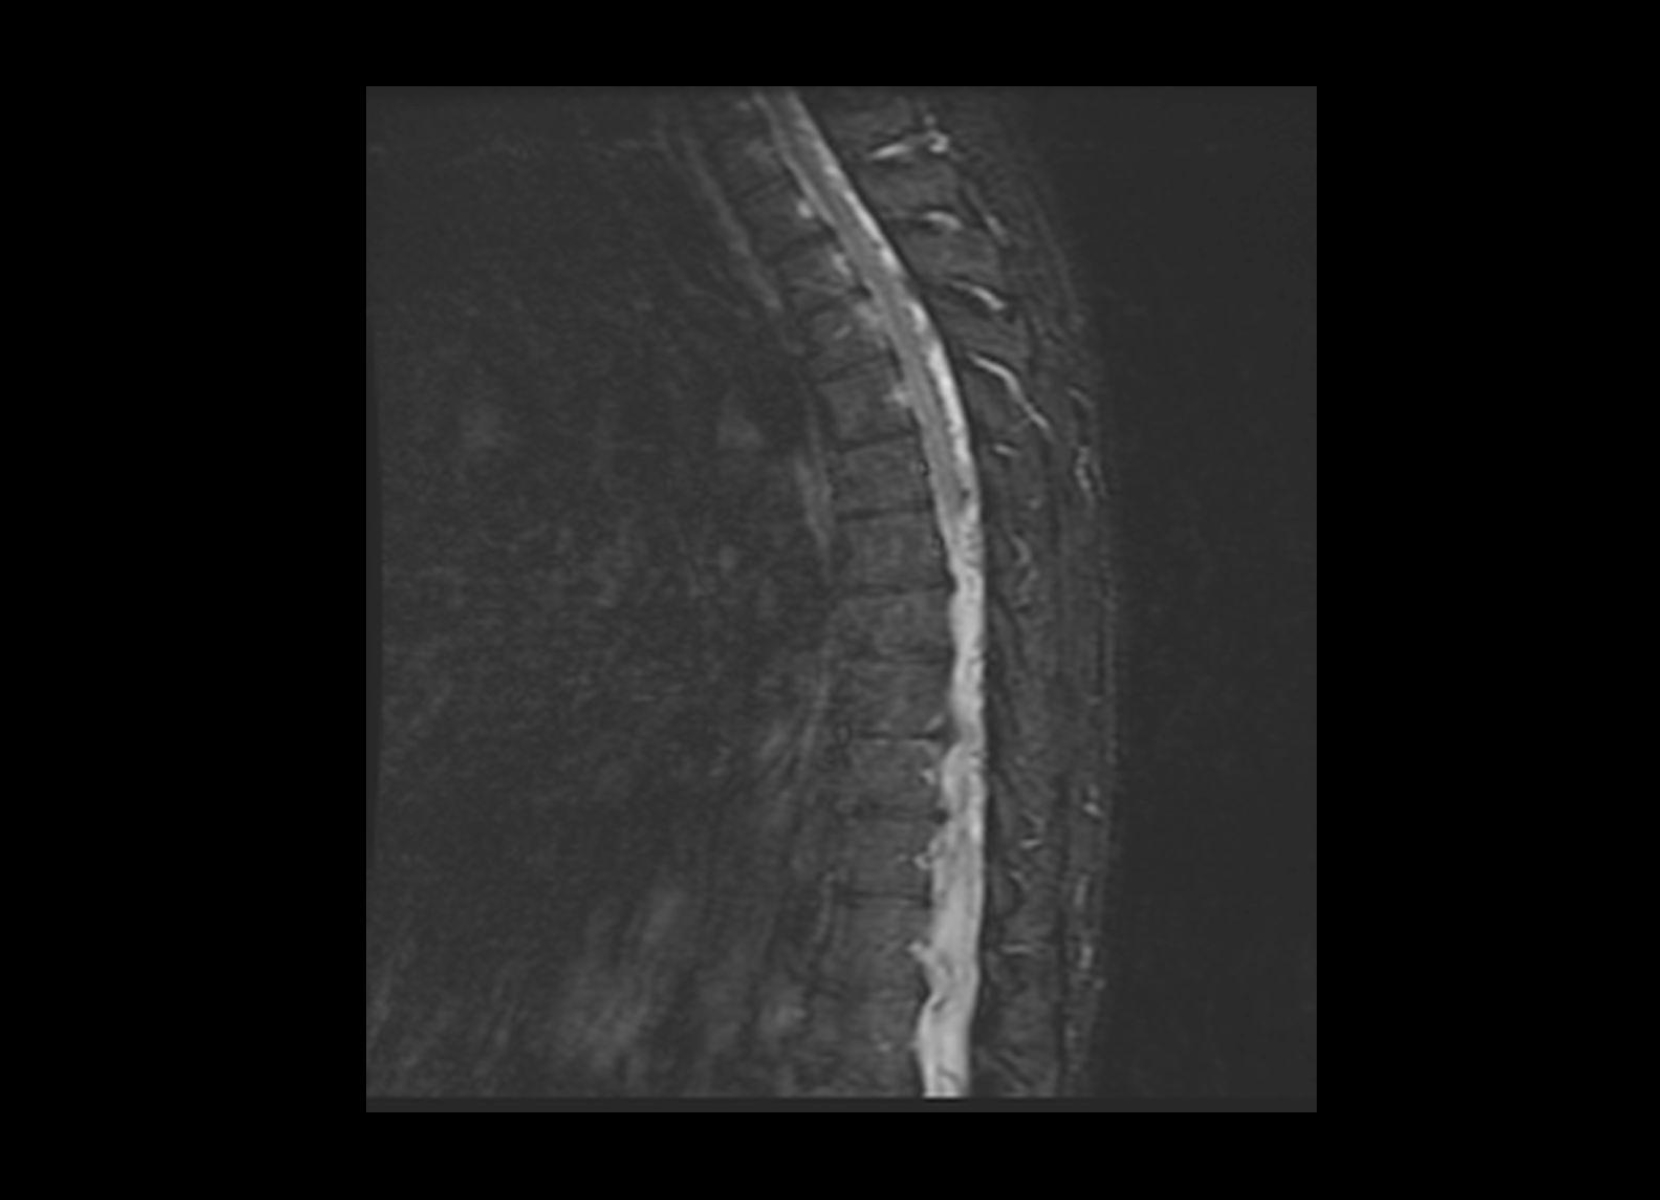

Conventional

STIR

SubtleSYNTH™

(Synthesized STIR)™

Trauma

GE 1.5T

C-spine